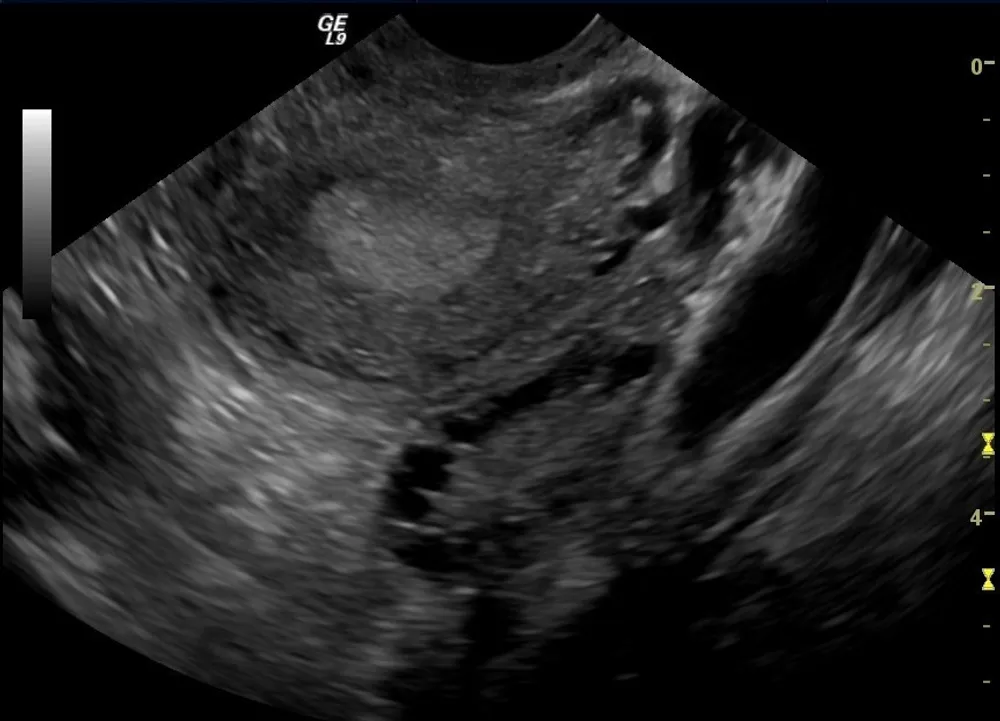

Décrit pour la première fois en 1935, le syndrome des ovaires polykystiques – ou syndrome de Stein-Leventhal – est une pathologie hormonale chronique et évolutive, dont la cause est inconnue, qui peut provoquer un déséquilibre hormonal : les femmes qui en sont atteintes ont un taux d’androgène beaucoup trop élevé par rapports aux normes biologiques. Ce déséquilibre hormonal entraîne un excès de follicules autour de l’ovaire, lesquels impliquent des cycles menstruels longs – voire très longs, parfois plus de 100 jours – et anovulatoires.

Le SOPK touche entre 8 et 13% des femmes “en âge de procréer” selon l’OMS, sans compter les femmes qui n’ont jamais été ou qui rencontrent des difficultés à être diagnostiquées. Ce dernier arrive souvent très tardivement, en moyenne au bout de 7 ans, et généralement pas avant le cinquième rendez-vous. En outre, jusqu’à 70% des femmes touchées par cette pathologie dans le monde ne sont encore pas diagnostiquées. Et encore faut-il supporter le long parcours du diagnostic et les rendez-vous médicaux marqués par l’expression de violences à destination des patientes, voire des violences gynécologiques et sexistes.